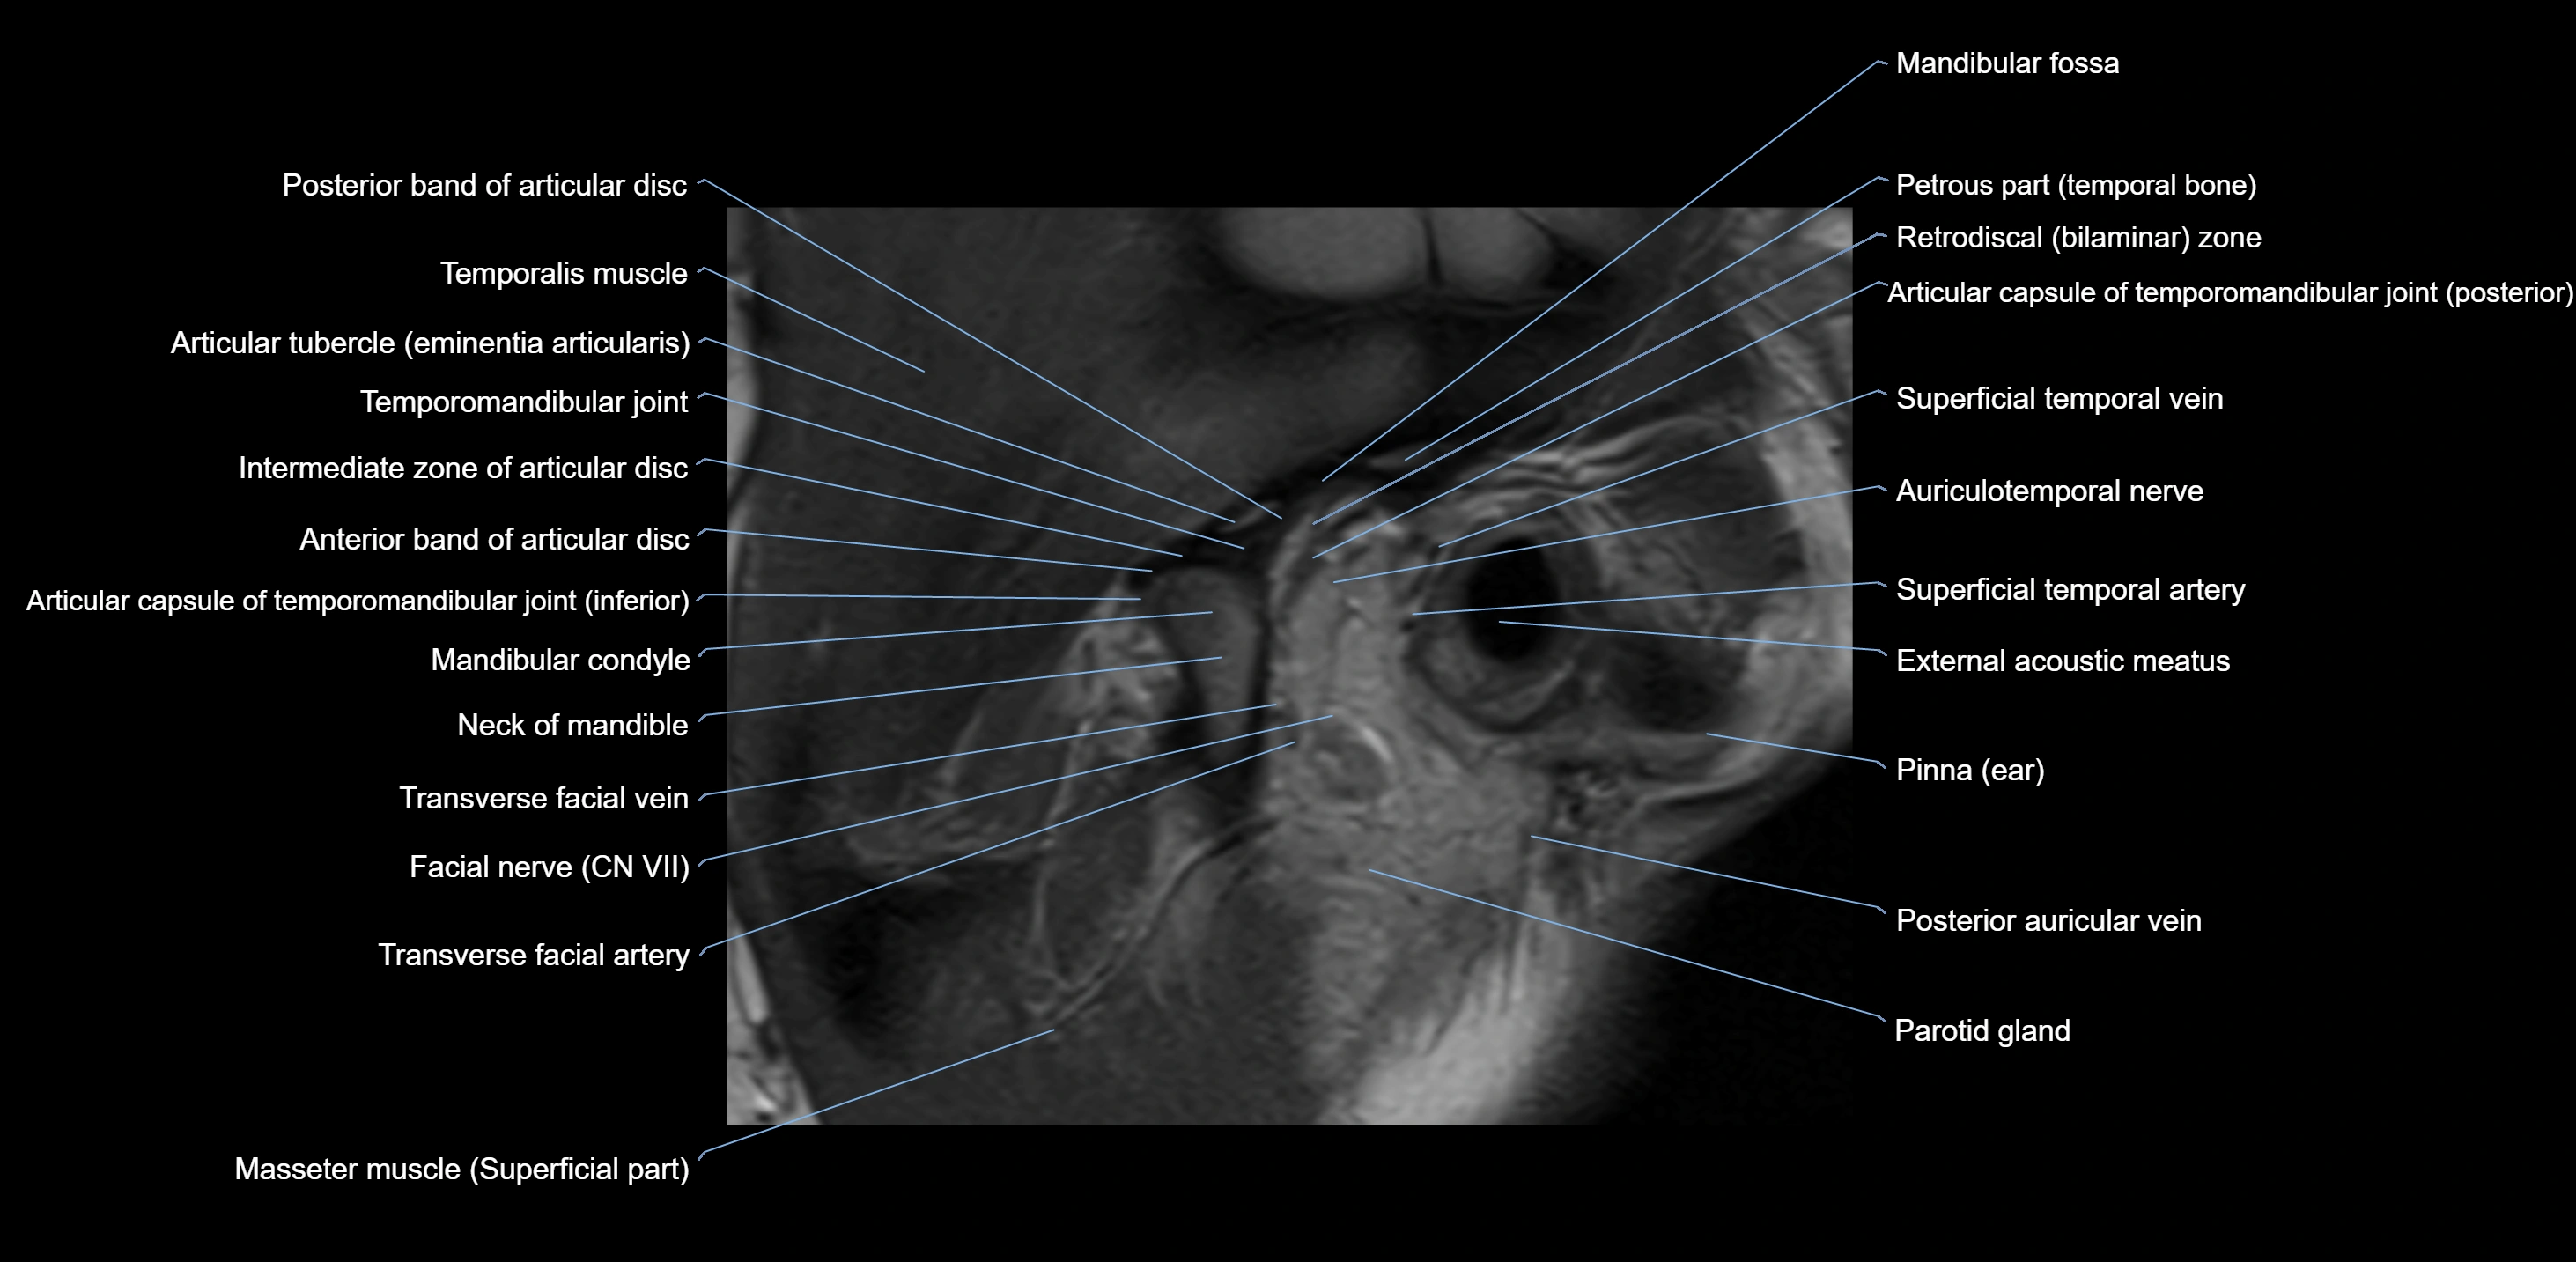

MRI appearance

T1-weighted images:

• Cortical bone: Low signal intensity

• Cancellous marrow: Intermediate to high signal depending on fatty content

• Teeth: Signal void structures

• Adjacent soft tissues: Normal gingiva and oral mucosa signal

T2-weighted images:

• Cortical bone and teeth: Low signal

• Marrow: Intermediate signal